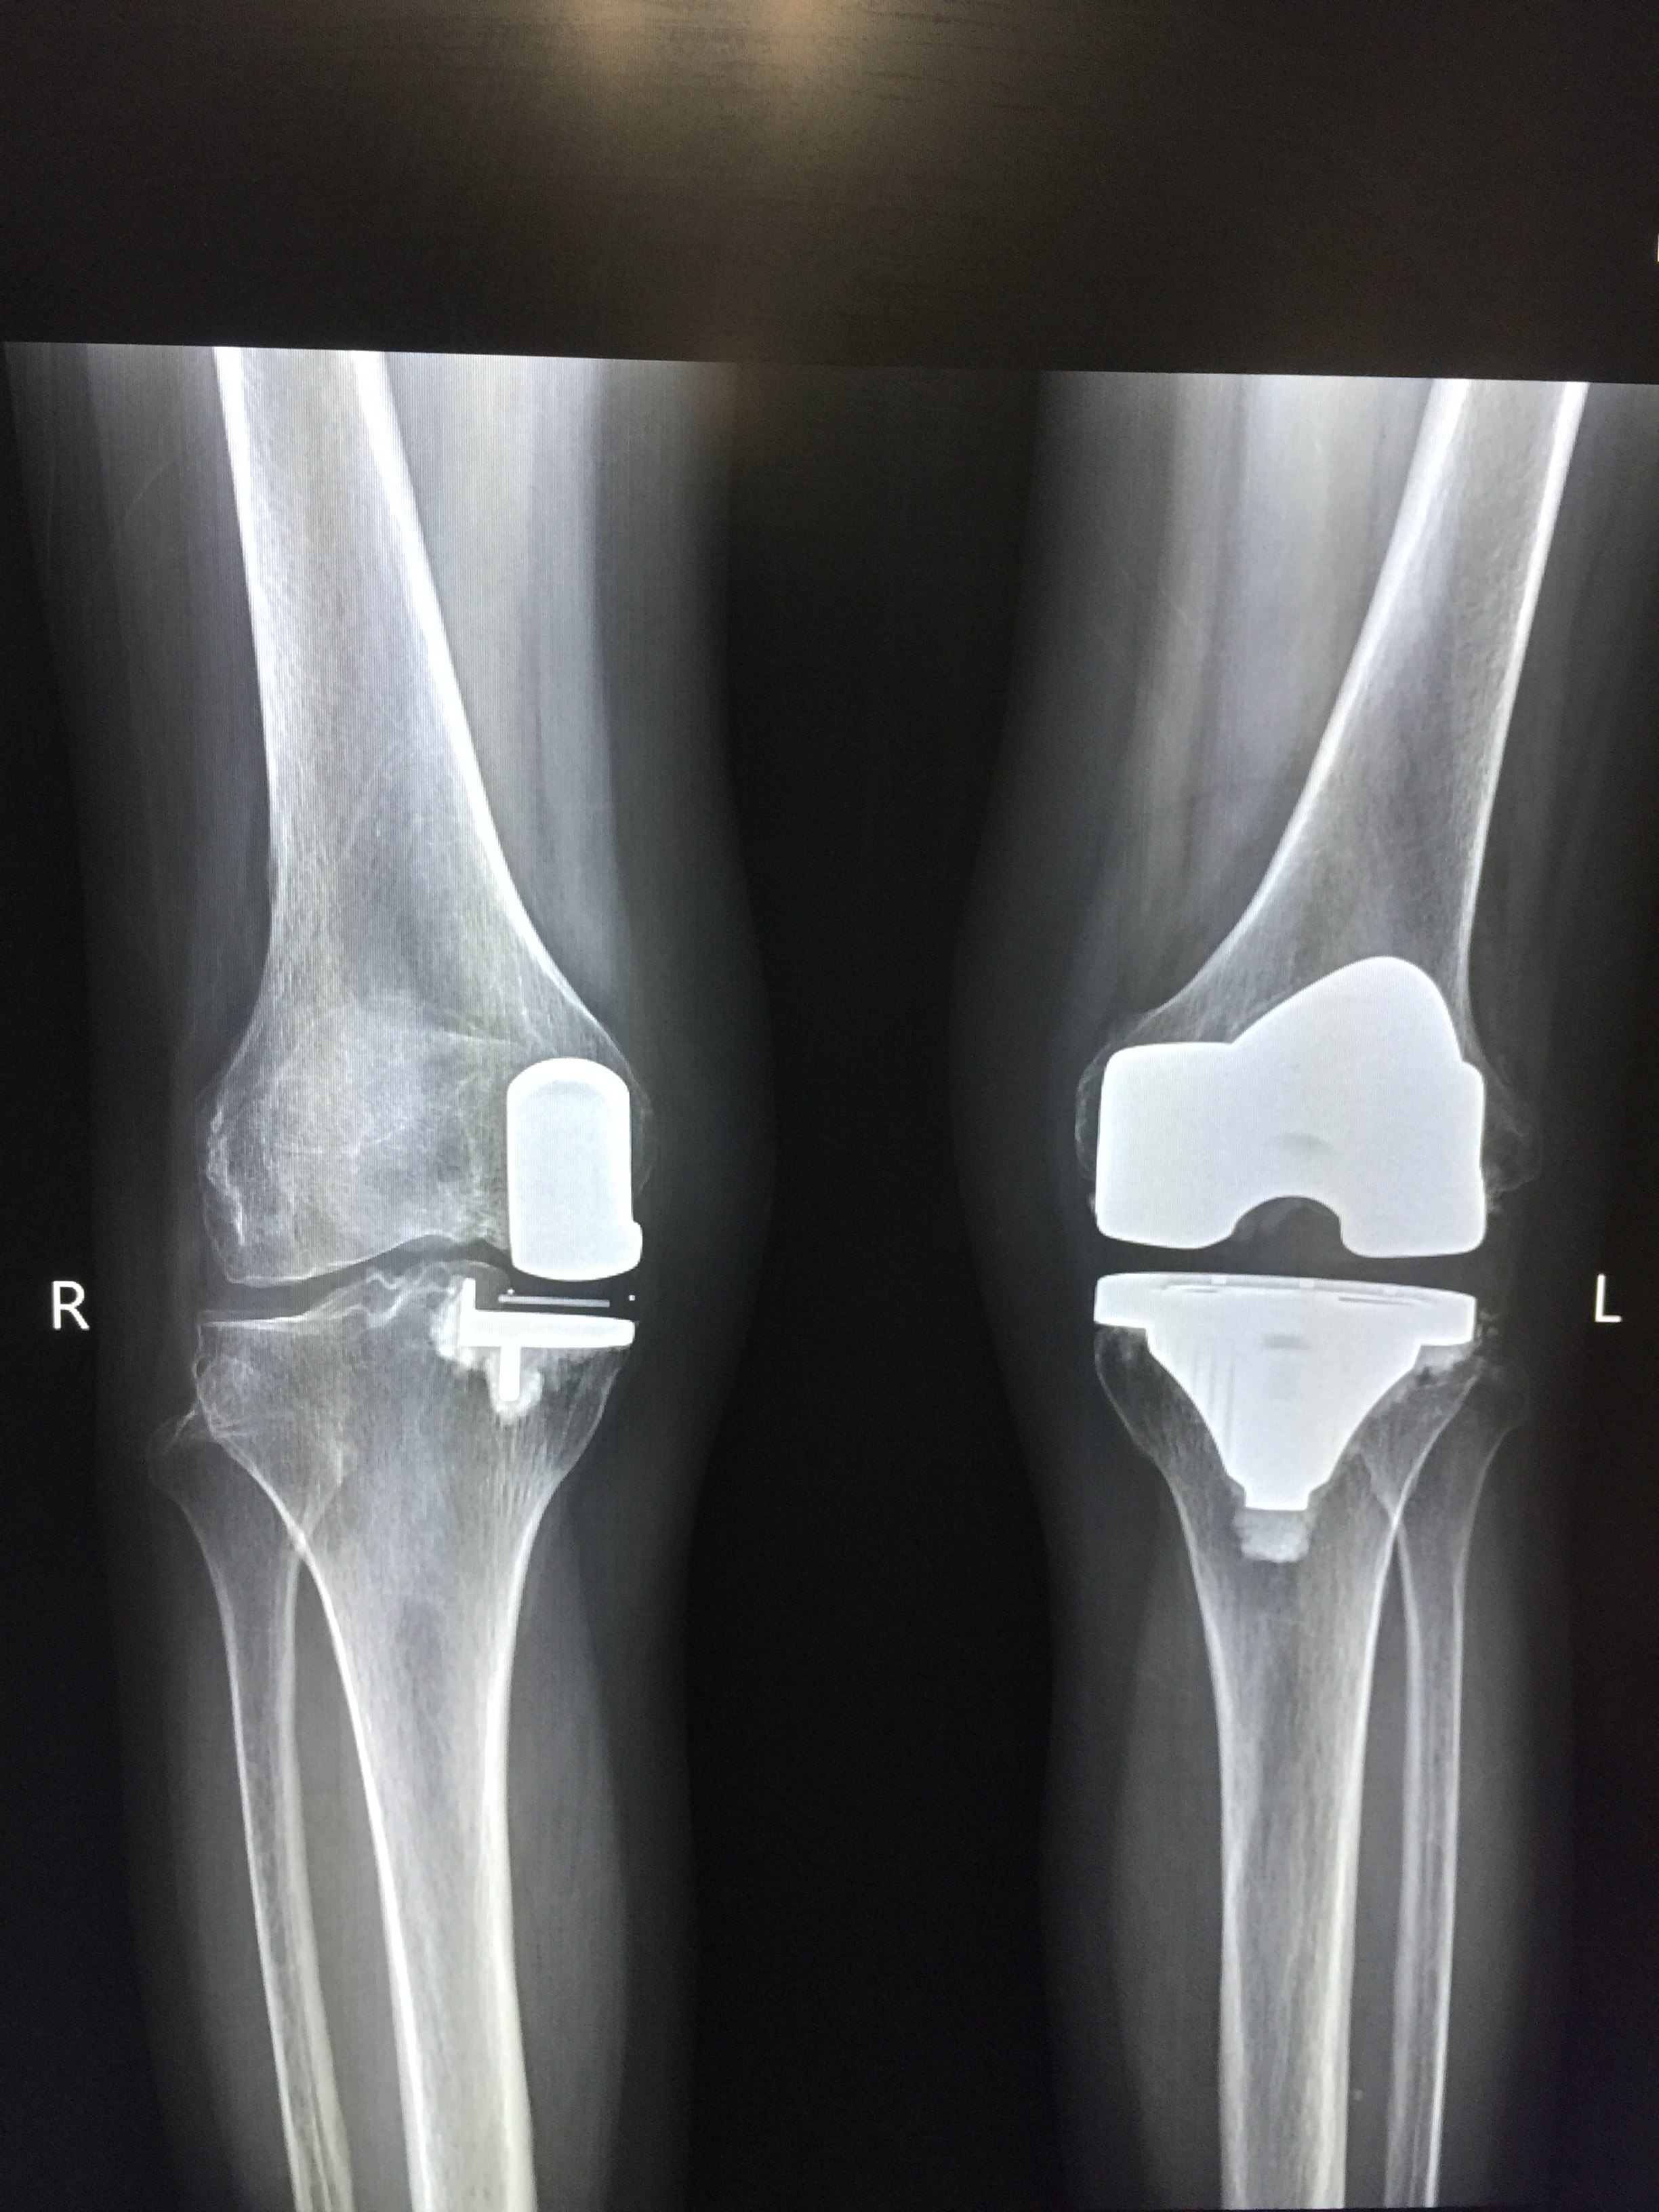

右膝关节置换手术

1280x880 - 221KB - JPEG

膝关节内侧单髁置换的临床要点

462x587 - 13KB - JPEG